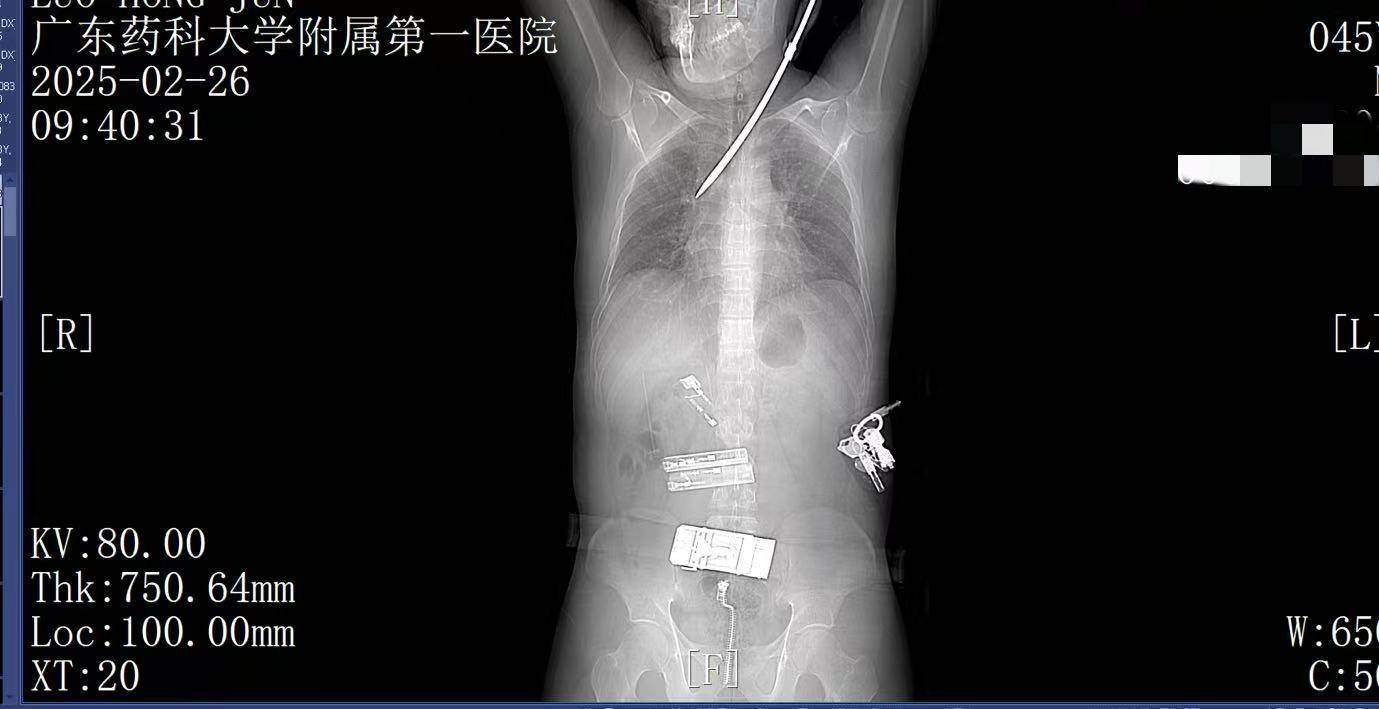

9:41,快速完成头+胸+腹部CT检查,经多学科会诊,明确螺丝刀异物刺入肺部。CT显示螺丝刀紧贴肋间血管、上肺后段动脉,尖端距右肺门仅2厘米,一旦贸然拔出螺丝刀,极有可能引发大出血,导致失血性休克甚至死亡,必须紧急手术。